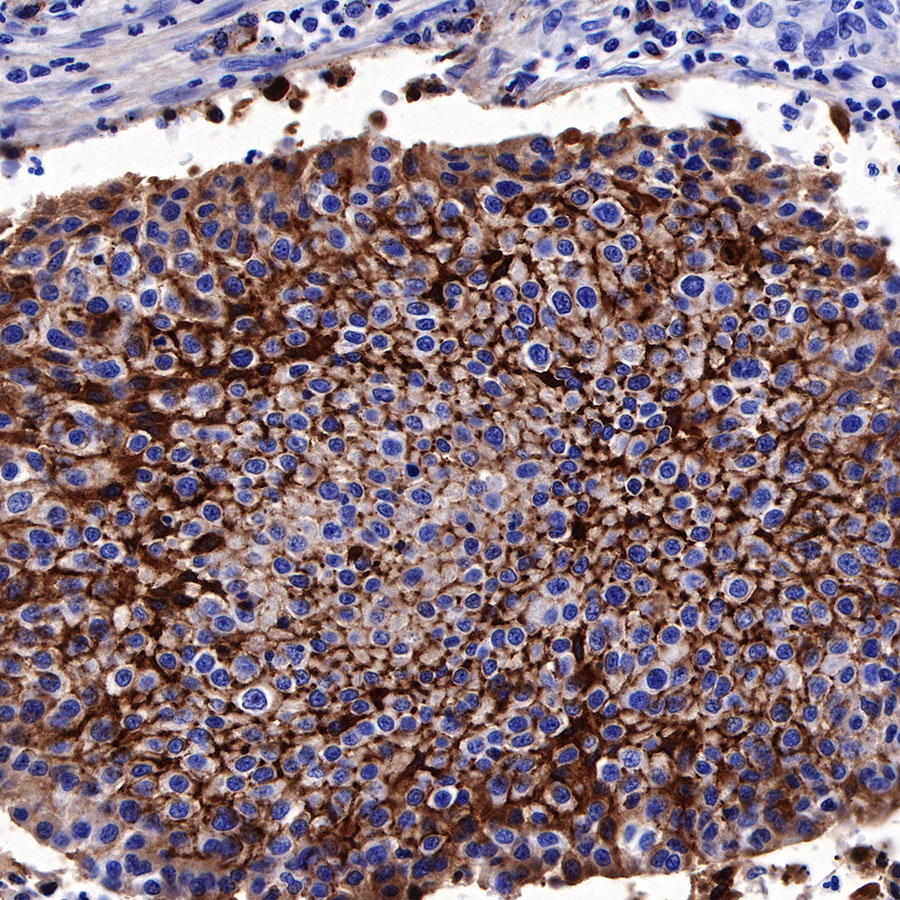

Immunohistochemistry

Syndecan-1 (CD138) is mostly restricted to epithelia, and bears heparan sulfate chains that are capable of interacting with a large array of polypeptides, including extracellular matrix components and potent mediators of proliferation, adhesion and migration. For this reason, it has been studied extensively with respect to carcinomas and tumor progression. Frequently, but not always, syndecan-1 levels decrease as tumor grade, stage and invasiveness and dedifferentiation increase. However, in some tumors, levels of syndecan-1 increase, but the characterization of its distribution is relevant. There can be loss of membrane staining, but acquisition of cytoplasmic and/or nuclear staining that is abnormal. Moreover, the appearance of syndecan-1 in the tumor stroma, either associated with its cellular component or the collagenous matrix, is nearly always a sign of poor prognosis [PMID: 33921767].